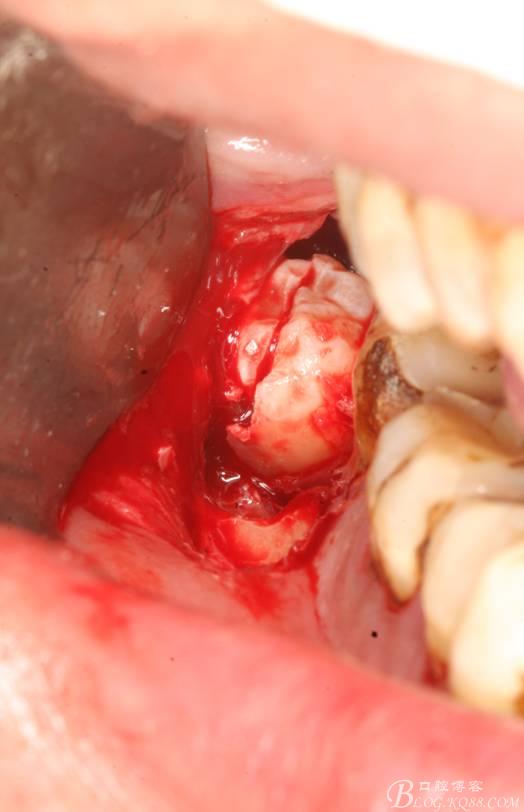

6.橫斷牙冠

7.取出牙冠

8.清理拔牙創(chuàng)